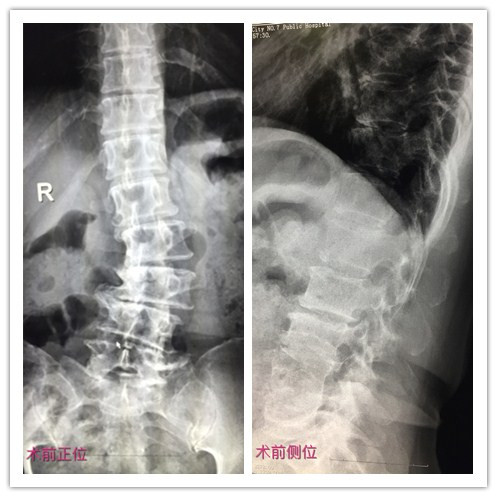

患者术前术后拍片对比

术后,患者腰腿疼痛症状明显缓解,拍片复查脊柱矫形满意,切口愈合良好,目前,患者正在康复中。